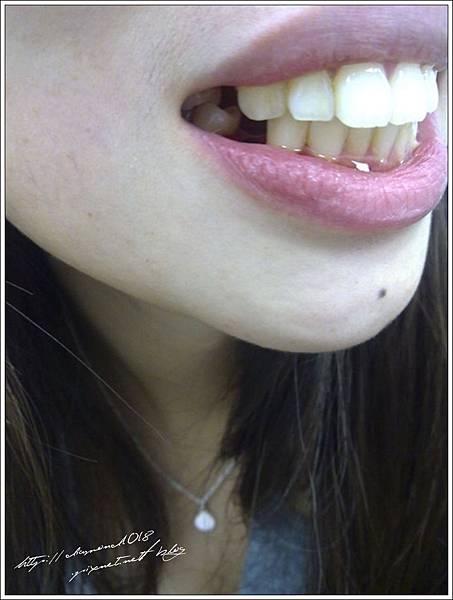

上圖是我拔牙前在診所廁所拍的 好像真的很爆牙齁XDD

拔牙我一共分兩次 一次兩顆這樣拔